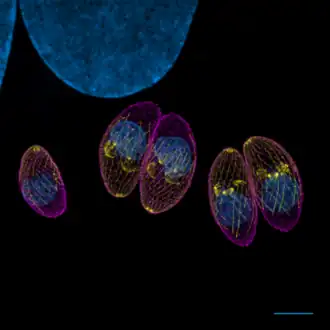

Toxoplasma gondii ne peut se multiplier de manière sexuée que chez les Félidés, qui constituent ainsi ses hôtes définitifs, bien qu’il puisse infecter tous les animaux homéothermes, dénommés hôtes intermédiaires. Le toxoplasme a un cycle complexe qui implique la transmission entre hôtes par des stades spécialisés pour l’invasion (voir figure) :

- le stade tachyzoïte, forme proliférative infectieuse chez l’hôte intermédiaire, se développe dans des vacuoles transitoires qui peuvent contenir jusqu’à 128 parasites ; cette forme peut se retrouver aussi chez le fœtus.

- le stade bradyzoïte, chez l’hôte intermédiaire, est contenu dans des kystes intracellulaires qui mesurent environ 100 µm de diamètre et contiennent plusieurs milliers de parasites ;

- le stade mérozoïte, chez l’hôte définitif, est le seul stade capable de reproduction sexuée ;

- le stade sporozoïte, résultat de la reproduction sexuée chez l’hôte définitif, est libéré dans l’environnement avec les déjections du chat dans des oocystes de 10 à 15 µm de diamètre qui contiennent 8 sporozoïtes.

Les stades sporozoïte et bradyzoïte correspondent à des formes de résistance et de dissémination du parasite car, dans une certaine mesure, les kystes et les oocystes protègent les parasites qu’ils contiennent des variations de température, de pH, etc. T. gondii peut alterner entre ces stades en fonction de son hôte et de son contexte, par un processus de différenciation.